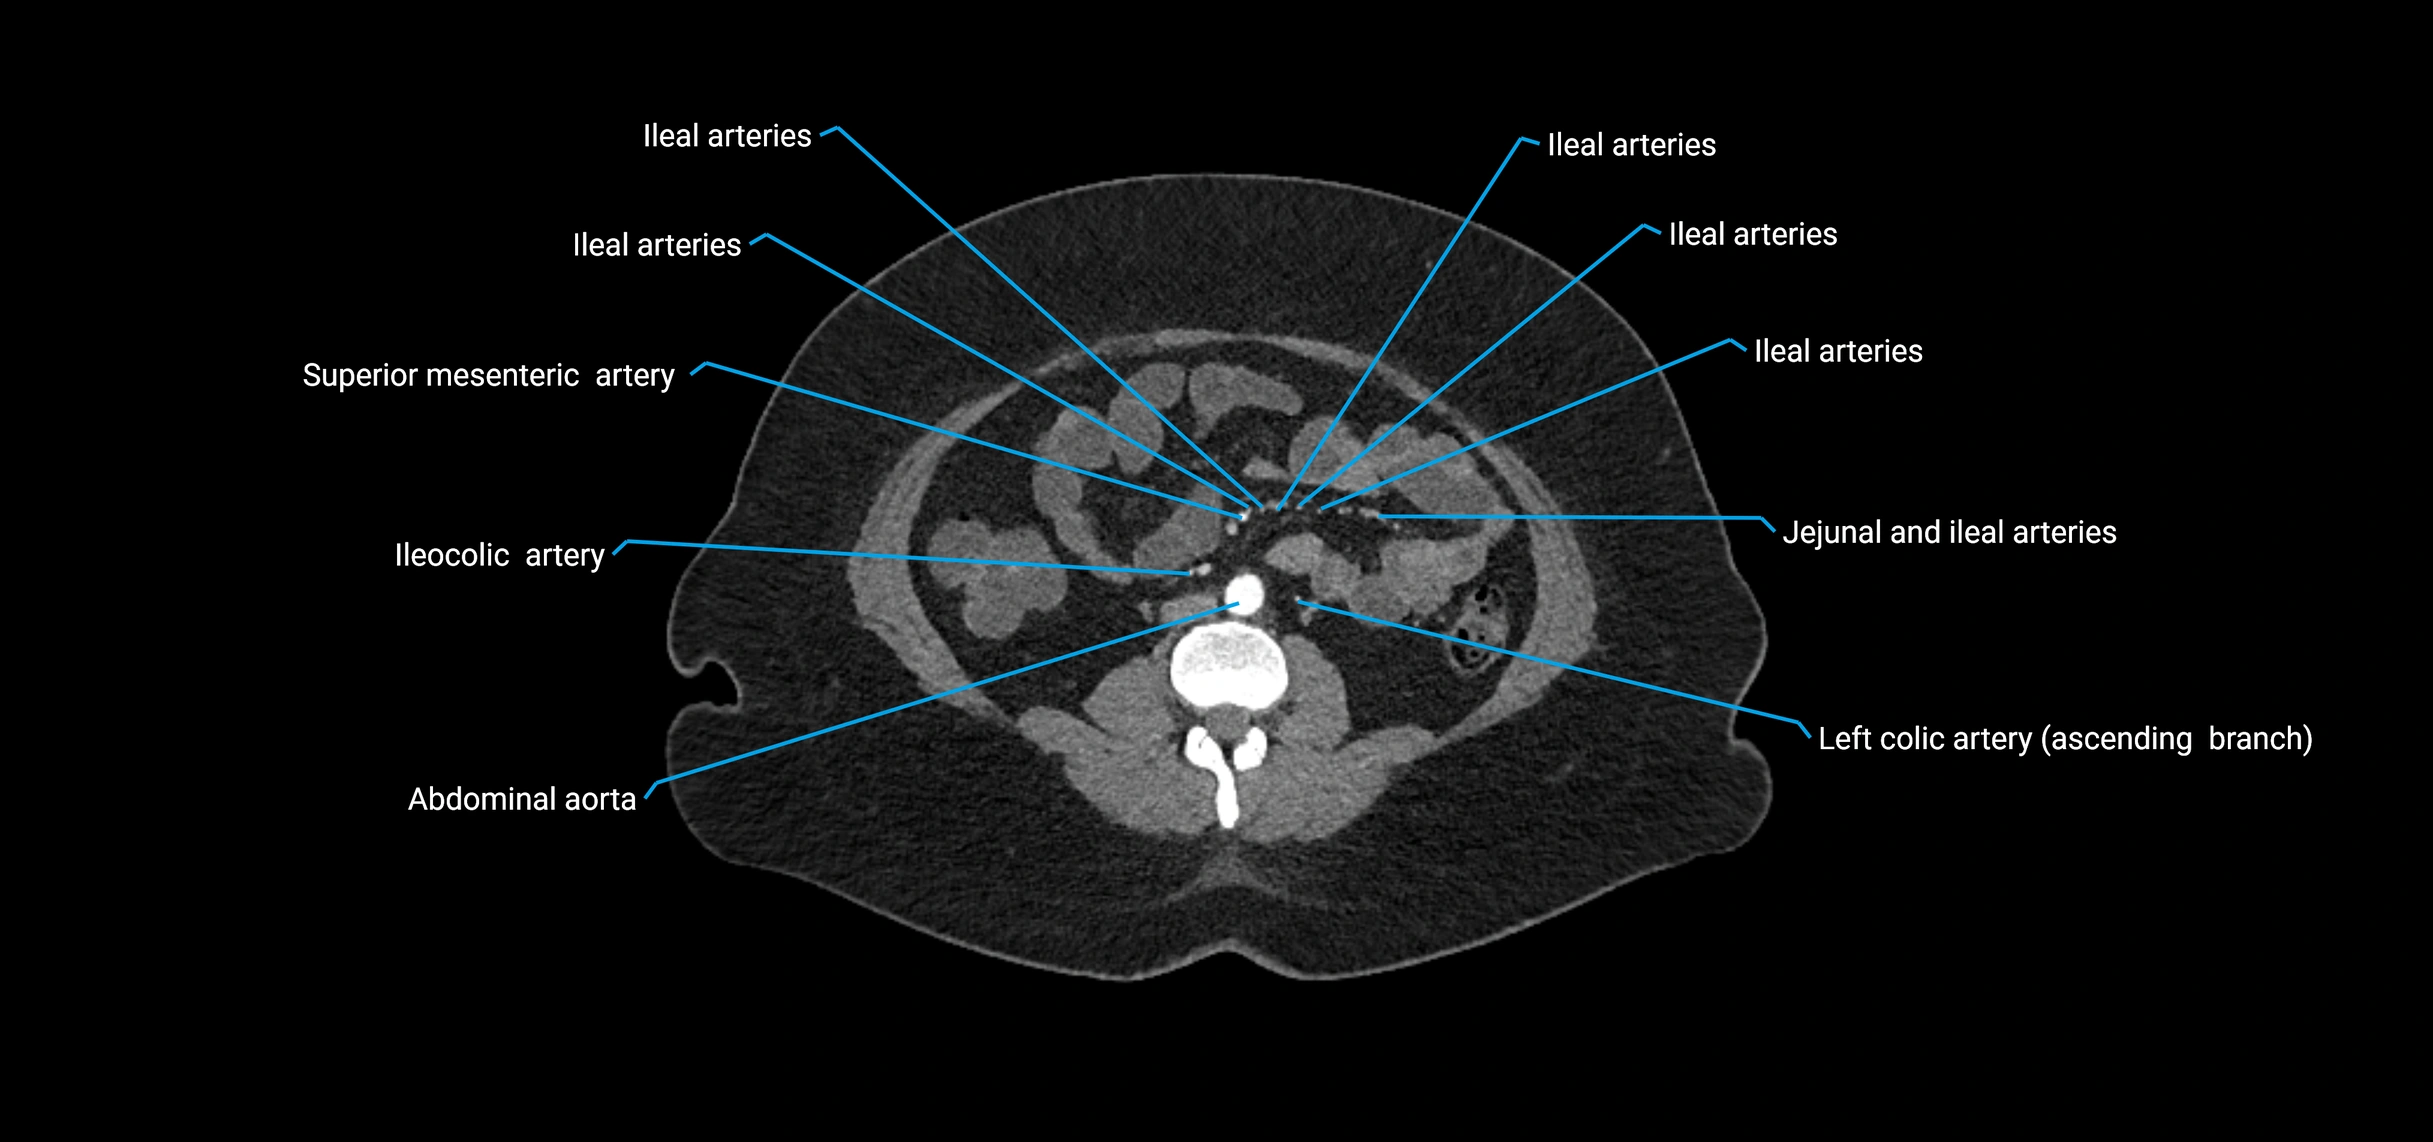

Contrast-enhanced CT (CTA):

• Gold standard for abdominal aortic imaging

• Provides excellent detail of lumen, wall, aneurysm, thrombus, and branch vessels

• Multiplanar and 3D reconstructions help in aneurysm measurement, stent graft planning, and dissection evaluation